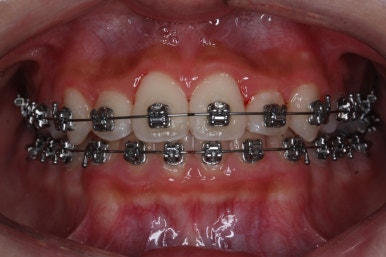

처음 내원 때의 입안 모습입니다.

영구치는 모두 맹출이 되어있었고 아랫니는 윗니에 비해 매우 가지런한 편이였습니다.

윗니 중에서도 앞니가 매우 삐뚤하고 특히 작은 앞니 양쪽 모두가 아래 앞니보다 안쪽에 들어가 있는 모습입니다.